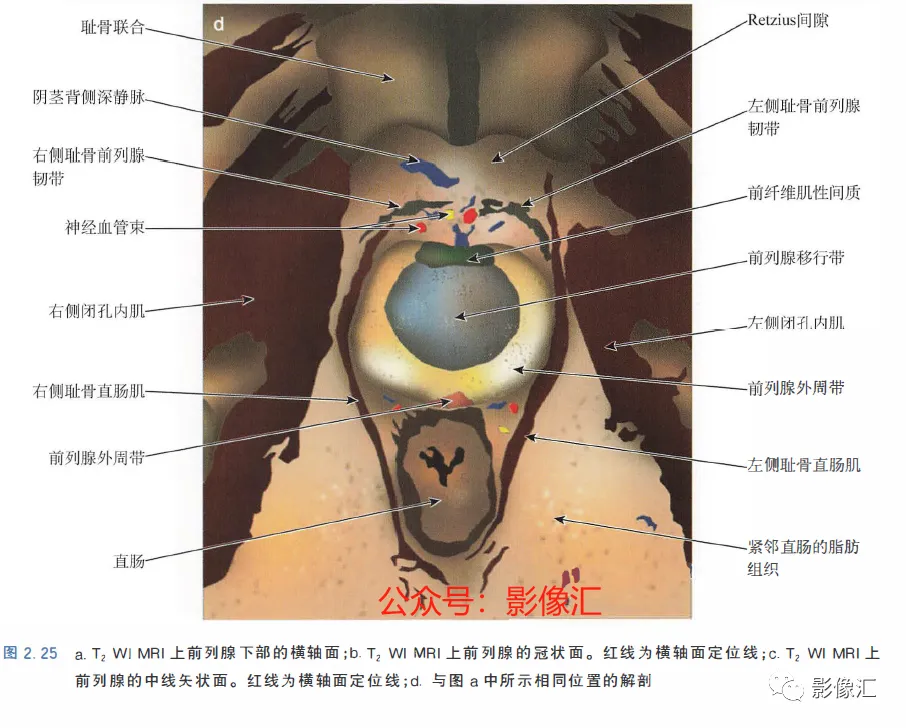

7. 前列腺下部水平的横轴面(图2.25)